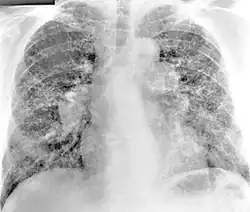

Im Röntgenbild des Brustkorbs zeigen sich unregelmäßige, knotige Veränderungen der Lungen. Bei etwa der Hälfte der Fälle findet sich ein Befall der Lymphknoten am Lungenhilus.